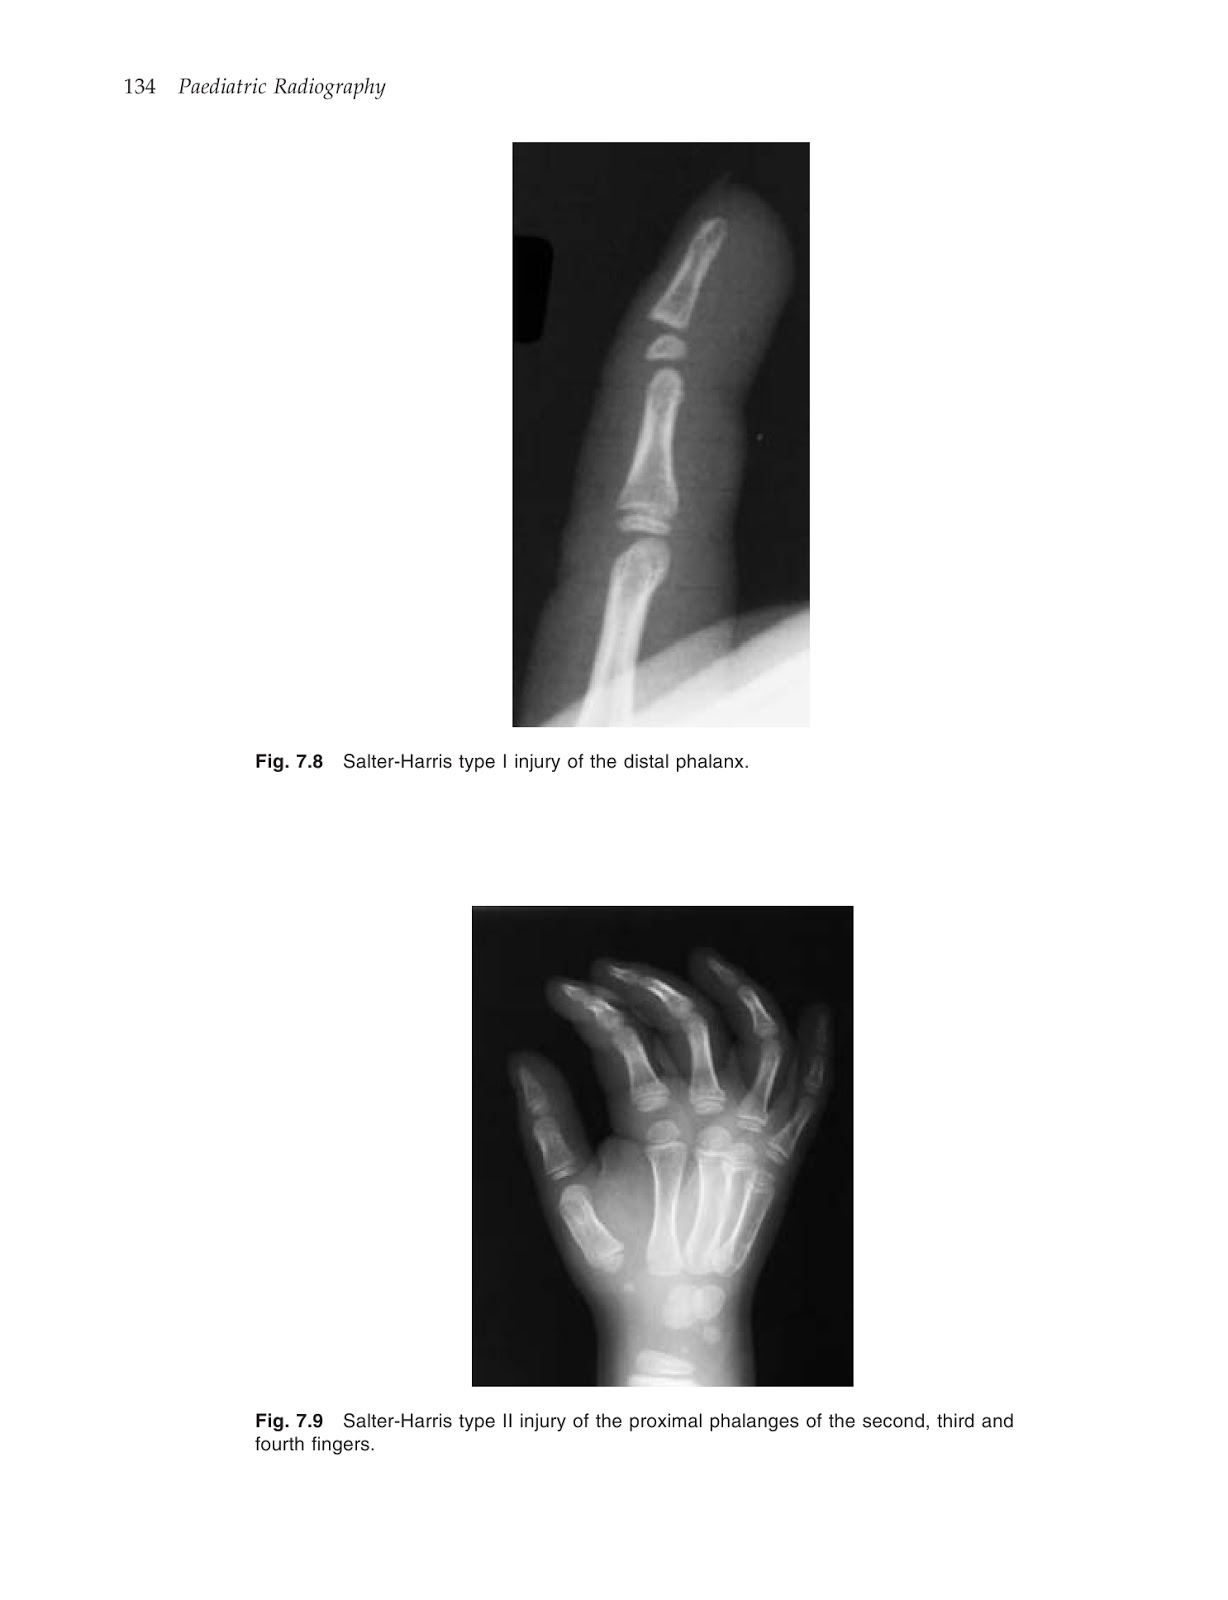

*التصوير الإشعاعي للأطفال (paediatric radiography) بواسطة MARYANN&STEPHEN BOYNES

التصوير الإشعاعي للأطفال (paediatric radiography) بواسطة MARYANN&STEPHEN BOYNES